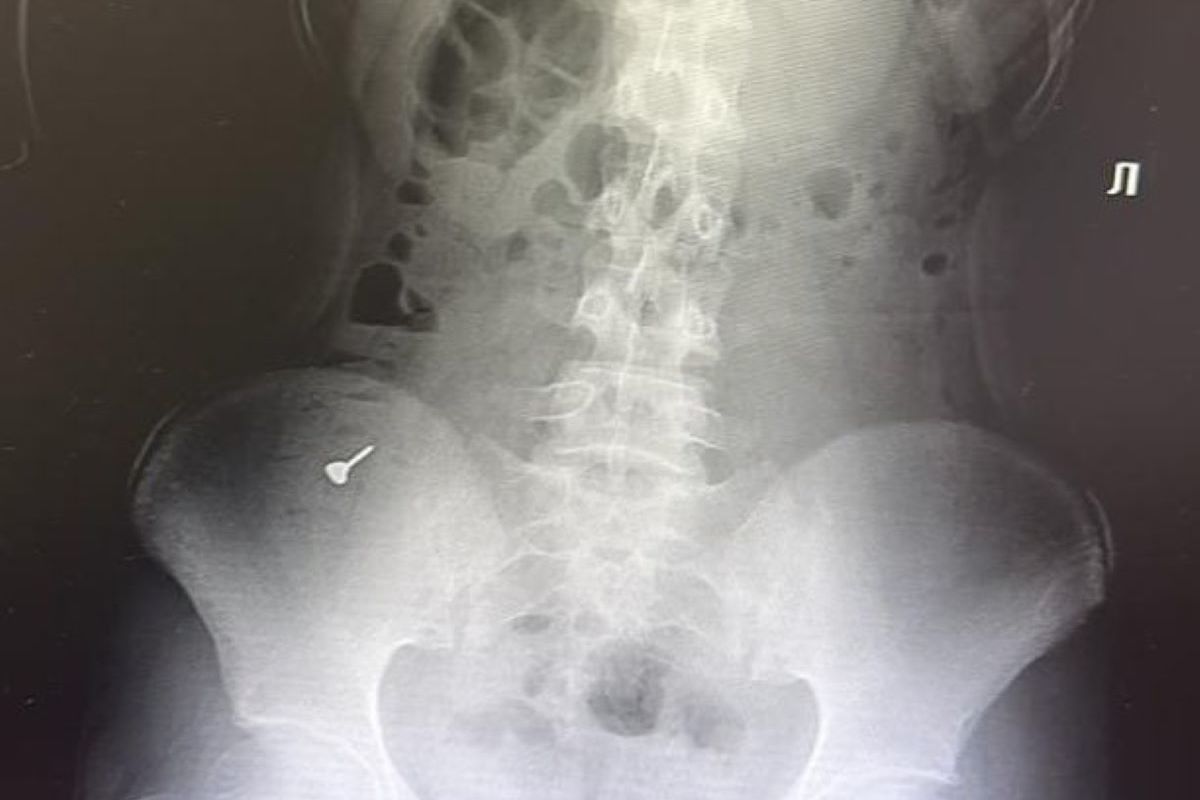

Раменские врачи удалили из кишечника 17-летней пациентки деталь от пирсинга. Девушка случайно проглотила украшение и пожаловалась на боли в животе, сообщает пресс-служба Минздрава Подмосковья.

В Раменскую больницу в сопровождении родителей поступила 17-летняя пациентка. Девушка проглотила деталь от пирсинга и жаловалась на сильные боли в животе. Диагностика показала наличие 3-сантиметрового металлического предмета, застрявшего в области слепой кишки.